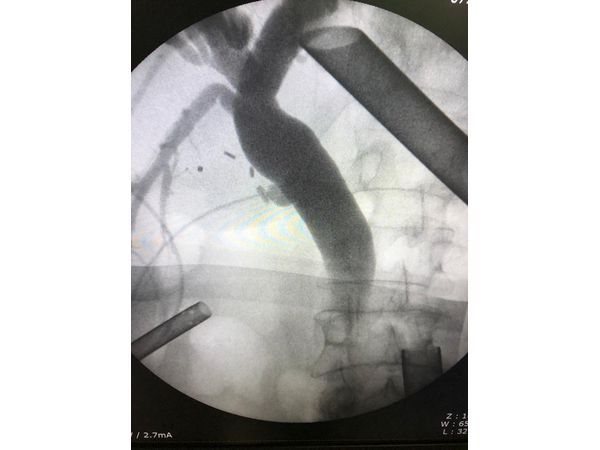

- Интраоперационную фистулохолангиографию — в желчные протоки ввели контрастное вещество, затем сделали рентгеновские снимки. Так подтвердили наличие крупного конкремента.

- Ретроградную холангиопанкреатографию с эндоскопической папиллотомией и холедохолитоэкстракцией. В ходе этой манипуляции через рот и пищевод в двенадцатиперстную кишку ввели гибкую трубку. Через неё пустили контрастное вещество и сделали рентгеновские снимки протоков желчного пузыря и поджелудочной железы. После этого рассекли проток, в котором находился камень, и извлекли конкремент.